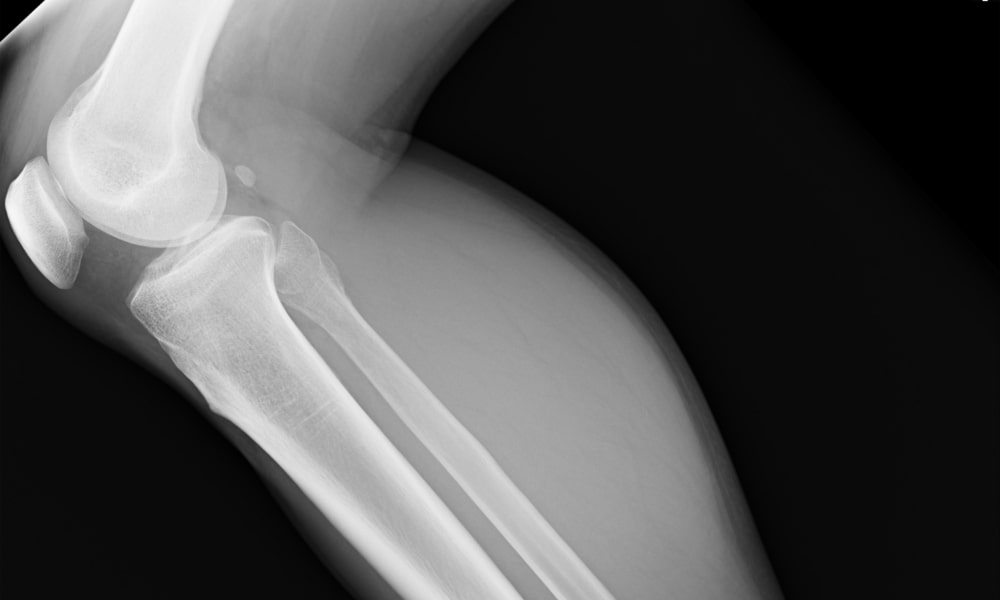

- レントゲンを撮ったが原因不明だった

膝のスポーツ障害

・オスグッド病:成長期のスポーツ少年に多く、膝下の脛骨粗面が痛む。

・ジャンパー膝(膝蓋腱炎):ジャンプ動作やダッシュで膝蓋腱に炎症が起きる。バスケ・バレー選手に多い。

・半月板損傷:膝の軟骨が損傷し、ひっかかり感や可動域制限が起きる。

・前十字靭帯損傷(ACL損傷):方向転換や着地で発生。スポーツ復帰に時間がかかる大きな外傷。

・ランナー膝(腸脛靭帯炎):ランニングで膝の外側が擦れて痛みが出る。

高性能なエコーで骨・靱帯・筋肉などを細かく観察できます。画像を評価して復帰目安などお伝えすることも可能です。